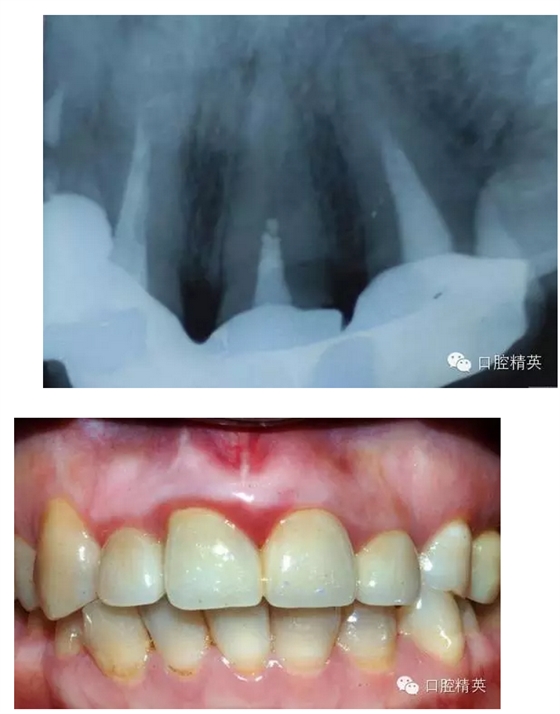

最近接到這樣一位患者,上前牙氧化鋯聯(lián)冠修復不足一年時間,現(xiàn)患者主訴左上前牙疼痛來診,檢查發(fā)現(xiàn)上前牙冷熱無反應(yīng),扣診(++),牙齦紅腫,探出血,冠邊緣不密合, X片示基牙全部已做根管治療,但是根管充填全部欠填。

病例1 由于根管充填不完善造成修復體拆除

修復后出現(xiàn)根尖周炎癥狀 根管再治療后病變愈合